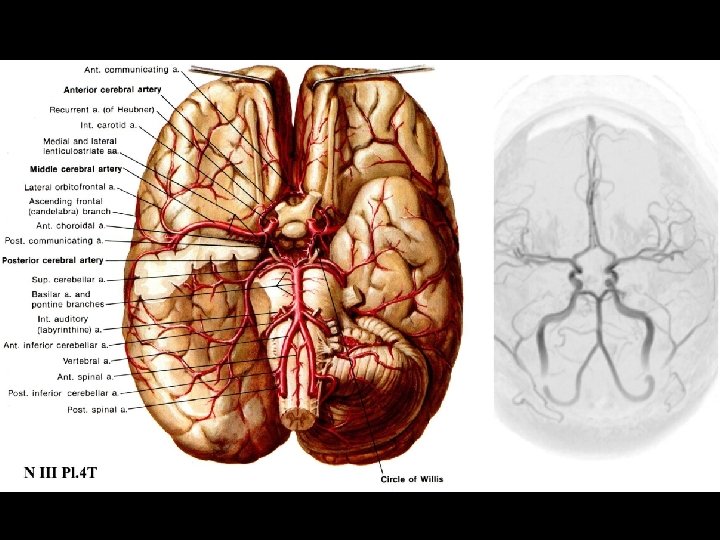

Arterial Blood Supply

Anterior circulation Internal carotid arteries Posterior circulation Vertebral arteries